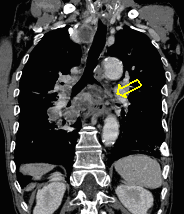

21. Left sided peripheral lung tumor

22. Central lung tumor with mediastinal lymphadenopathy. CT coronal and sagittal reconstructions.

70 year old man, COPD, hoarse. Right hilar mass, bronchoscopy was negative.

The larynx is rotated to the right, no motion of the right side of the larynx can be observed, swollen left plica ventricularis area.

CT: 13x11 mm large nodular mass in the left 10th segment. Bilateral hilar lymphadenomegaly with central hypodensity. A 34x21 mm large lymph node conglomeration can be observed in subcarinal location (peripheral contrast enhancement). Lymphadenopathy in the aortopulmonary window (15 mm large), and a 26 mm large lymph node can be observed in paraaortic location above the trachea bifurcation which has an esophagus-compressing effect. In the superior chest aperture there is a 38x28 large fused lymph node conglomerate which causes the left shift of the esophagus and trachea.